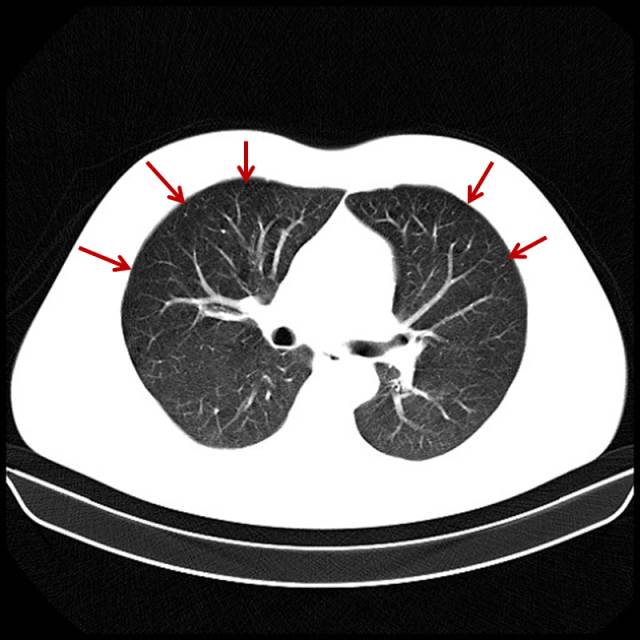

吸烟导致的重度肺气肿

男,72岁,吸烟史。

图片

图8

双肺布满小无肺纹区。这类患者气短已经相当明显,已经意识到与吸烟有关。只要一解释,一般都会立马戒烟。此类患者更多的是非常紧张,不断地询问:有什么好方法?能治好不?要知如今何必当初。其实年龄越大越紧张。